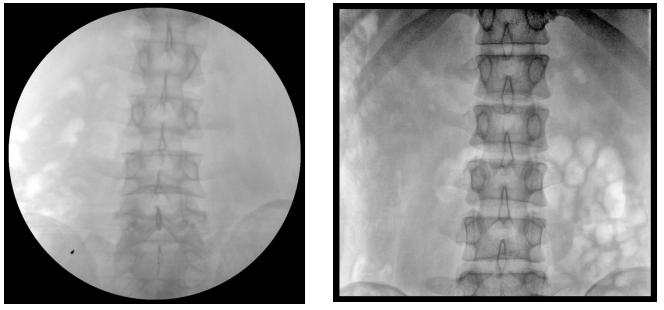

【產品臨床圖片】